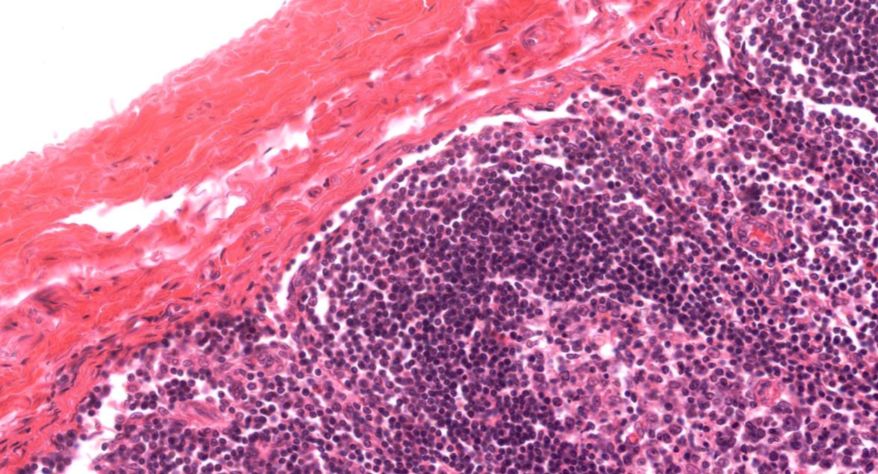

2 淋巴结